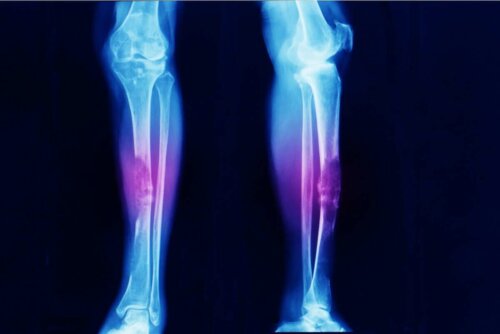

- الساركوما العظمية، هي سرطان العظام كما يشير اسمها.

ورم الساركوما السرطاني ليس شائعًا. في الواقع، تشير دراسات مختلفة إلى أن الساركوما العظمية (ورم في الهيكل العظمي) تمثل 0.2٪ فقط من جميع السرطانات الخبيثة. وهذا يعني حدوث حوالي ثلاث حالات لكل مليون شخص كل عام.